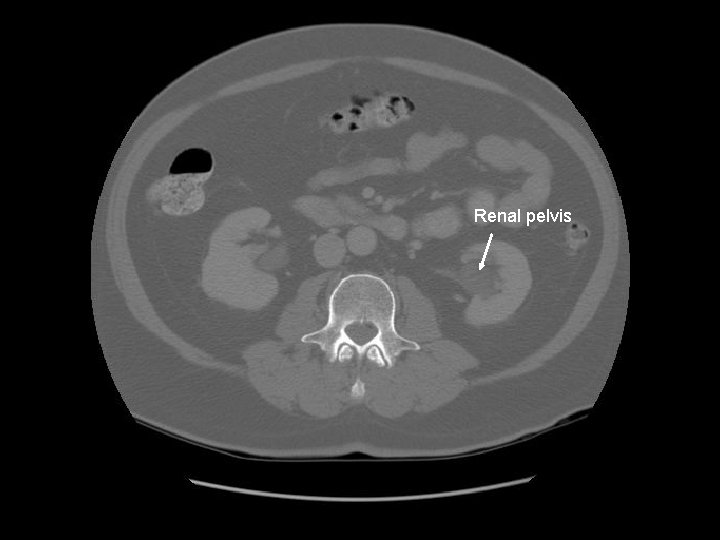

Kidney Right Kidney

Descending colon Right

Renal pelvis

Ascending colon Right colon with fecal material.

Abdominal aorta about to bifurcate.